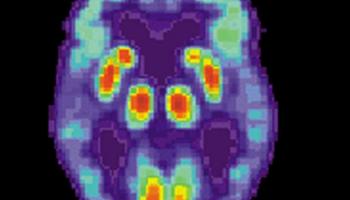

الدراسات التي أجريت على فأر ألزهايمر أظهرت نجاح اللقاح الجديد في استهداف الجزيئات السامة، وتحقيق تأثيرات مناعية قوية